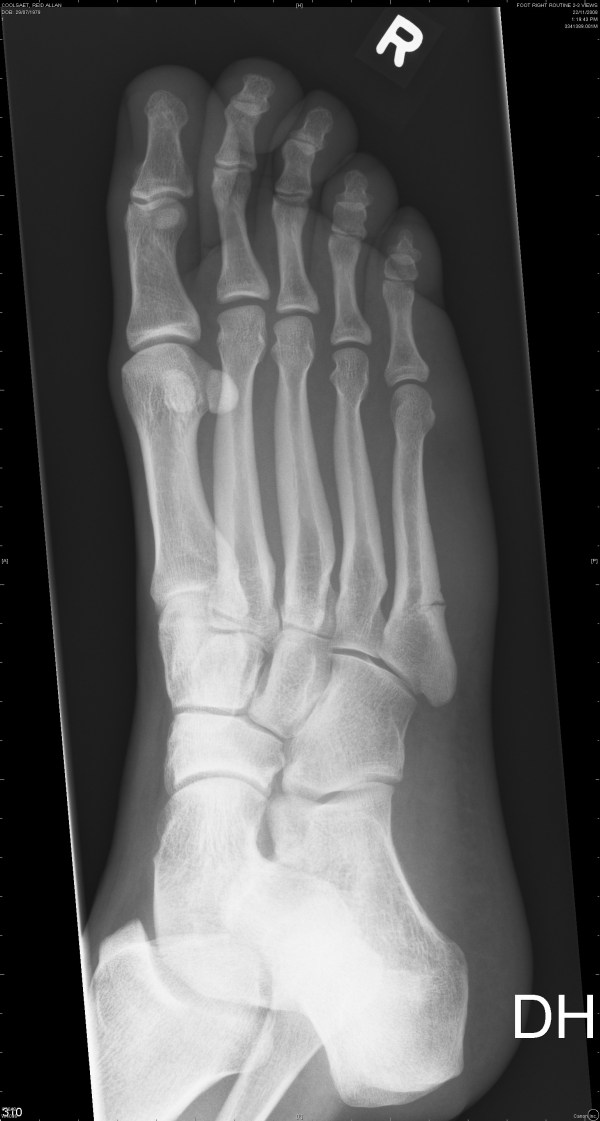

Below are three X-rays in chronological order from the day I broke my foot until yesterday (Jan. 20th).

Below is an X-ray from January 20th, 2009. You can see there isn’t such a gap anymore and there is some good calcification going on. The inside portion of the bone is healed (it’s easier to see with the viewing program which allows high resolution magnification). When I look at this image I think “my foot feels better than that“.